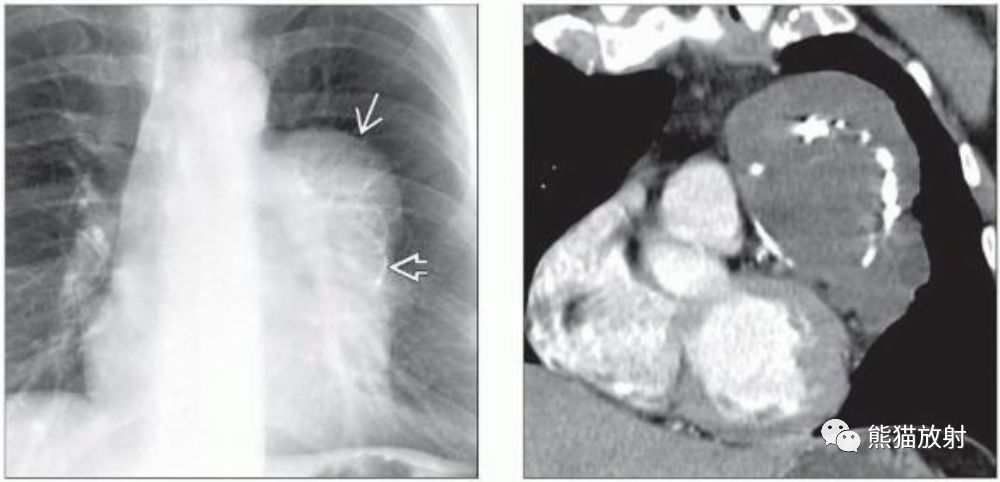

(左)成熟性畸胎瘤患者的PA胸片显示右侧心膈角球状肿块,内见弧形和圆形钙化。由于影像上有明显的钙化,在鉴别诊断中应考虑成熟性畸胎瘤。

(右)同一患者的轴位CECT显示右侧心膈角肿块,内见脂肪、液体、软组织和钙化。纵隔畸胎瘤的钙化通常呈环状、线状或粗颗粒样。

(左)成熟性畸胎瘤患者的PA胸片显示左前纵隔分叶状肿块伴弧形钙化。

(右)同一患者的冠状CECT显示类圆形肿块,不均匀低密度,边缘有分叶,内见弧形钙化。虽然未见脂肪密度,但根据病变的形态学特征和钙化样式考虑成熟畸胎瘤。